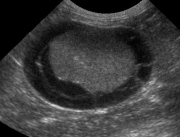

The right kidney is markedly enlarged, with a rounded shape. It is distorting the abdominal wall on the v/d projection and displacing the ascending and transverse colon medially and ventrally. The left kidney also has an abnormal shape, with reduced length and increased width.

On ultrasound images, both kidneys were surrounded by large cystic structures filled with echogenic fluid. There are fine septae visible in the pseudocyst surrounding the left kidney. Drainage of both collections of fluid were clear and colorless except for the last 15 ml from the right kidney, which was hemorrhagic. Both kidneys were small and irregular with poor corticomedullary distinction.

Bilateral perinephric pseudocysts and chronic renal disease.